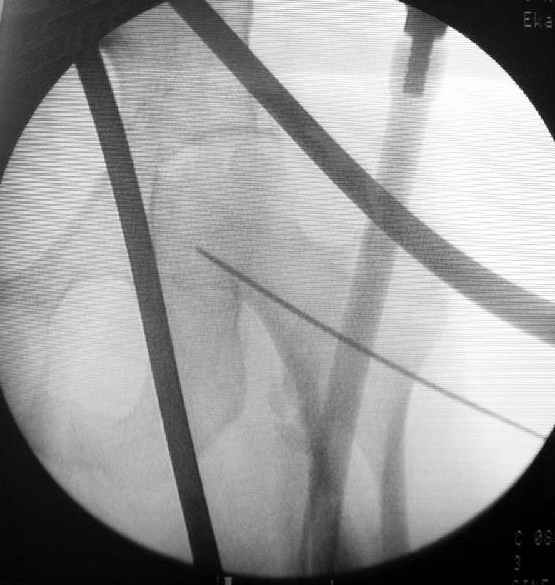

Наш туземный подход - flat radiolucent table и спицевой дистрактор.

DK> Чтобы не расколоть чрезвертельный перелом провели временную спицу

DK> ближе к переднему кортексу,

Мы обычно проводим спицу ближе к заднему кортексу - иногда бывает, гвоздь смещается кзади, за фрагменты, особено при многооскольчатых переломах...

DK> из малого разреза костодержатель для репозиции,

Это тоже не делаем. Разве что иногда приходится шилом подтолкнуть промежуточный фрагмент, если он перекрывает вход в дистальный отломок. Но костедержатель засовывать - зачем??? Ведь при введении гвоздя репозиция происходит "автомагически"?